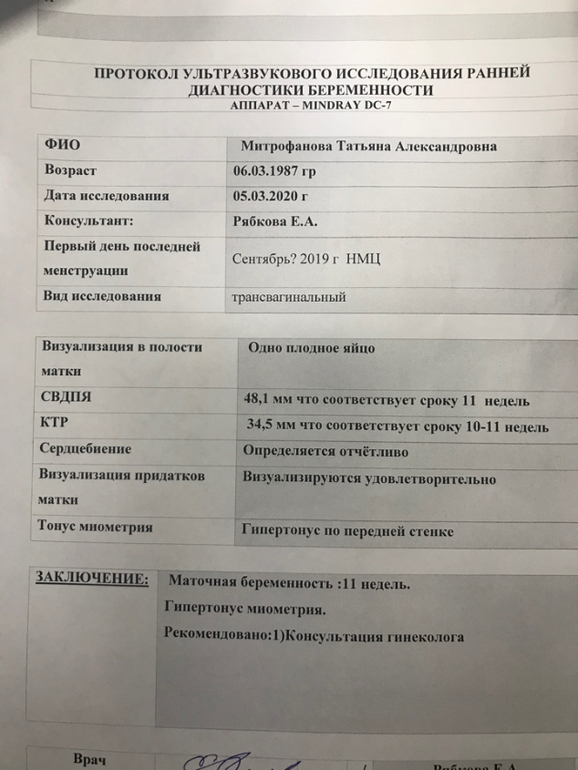

В декабре я поругалась с мужем и уехала в гости к маме в другой город, но раздобрела и мы благополучно помирились, потом новый год, каникулы, снова работа и я понимаю что грудь мать ее опять растет как в тот раз. Я была абсолютно уверена, что я опять беременна. И опять без месячных, без цикла. Купила тест, 2 полоски, на узи маленькое пятнышко и срок 2-3 недели. Это шок. Потому что зб она преследует все равно. Ушла на больничный на месяц.

13 марта у меня первый скрининг. А вчера я встала на учет, делала внеплановое узи, так как беспокоит боли внизу живота, в копчике, еще где-то непонятно где.(но на самом деле я просто тупо делаю узи почти каждую неделю потому что очень боюсь не услышать стук сердечка).

Не всё гладко. к сожалению. Появилась миома, но Г сказала ничего страшного, будем наблюдать. И бесконечный гипертонус, который видимо приводит плодное яйцо в жуткое состояние (на картинке). Я смотрю на фото узи других и вижу, какие у них красивые овальные и круглые домики, а у меня вечно все через ж... Сначала писали ПЯ неправильной формы, потом деформированное, короче какое-то оно странное. Видела вчера на узи как малышу тесно в таком(( Сказали, что пя все равно тоже растет и должно быть всё нормально.

Остальные анализы в норме, ставлю папаверин 3 раза в день, утрожестан 200 3 раза в день, магний В6 форте 3 раза в день, фемибион 1, еще добавили вчера валерьянку в таблетках на пару недель)))